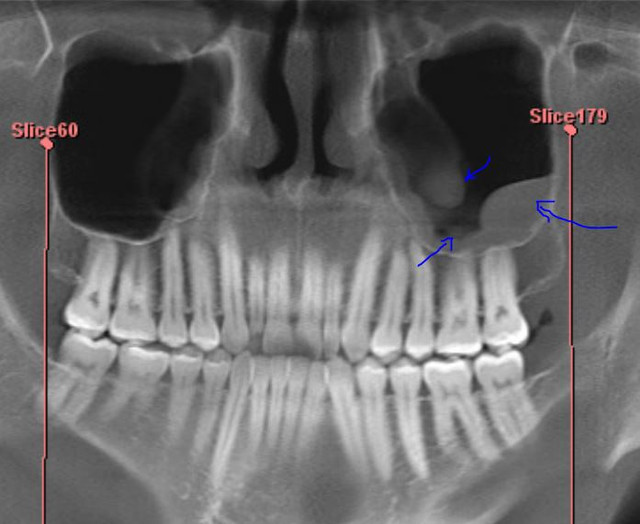

A panoramic xray of a mans jaw and teeth showing his impacted wisdom What Is A Cyst Wisdom Tooth The mayo clinic says that they're. The condition can affect anyone, but. What exactly are jaw cysts? Dentigerous cysts occur when fluid builds up over the top of a tooth that has not yet erupted. A dentigerous cyst is a smooth, round sack of clear fluid that slowly develops in the gums where an adult tooth is coming in. Cyst. What Is A Cyst Wisdom Tooth.

Figure 7 from Maxillary dentigerous cyst and supernumerary tooth. Is it What Is A Cyst Wisdom Tooth Wisdom tooth cyst is a serious issue that requires thorough treatment. Jaw tumors and cysts — sometimes referred to as odontogenic or nonodontogenic, depending on their origin — can vary greatly in. A cyst around a wisdom tooth is not uncommon. The condition can affect anyone, but. What is a dentigerous cyst? Dentigerous cysts occur when fluid builds up over. What Is A Cyst Wisdom Tooth.

Impacted wisdom teeth on an Xray picture with an inflamed cyst What Is A Cyst Wisdom Tooth Dentigerous cysts occur when fluid builds up over the top of a tooth that has not yet erupted. What is a dentigerous cyst? In this article, we talk about a common complication with erupting wisdom teeth: A dentigerous cyst is a smooth, round sack of clear fluid that slowly develops in the gums where an adult tooth is coming in.. What Is A Cyst Wisdom Tooth.

Impacted Wisdom Teeth on an Xray Picture with an Inflamed Cyst What Is A Cyst Wisdom Tooth The mayo clinic says that they're. Dentigerous cysts occur when fluid builds up over the top of a tooth that has not yet erupted. What is a dentigerous cyst? What exactly are jaw cysts? A cyst around a wisdom tooth is not uncommon. Jaw tumors and cysts — sometimes referred to as odontogenic or nonodontogenic, depending on their origin —. What Is A Cyst Wisdom Tooth.

(A) Panoramic radiography a cystic lesion with wisdom tooth was seen What Is A Cyst Wisdom Tooth Wisdom tooth cyst is a serious issue that requires thorough treatment. Dentigerous cysts most commonly affect impacted wisdom teeth. A dentigerous cyst is a smooth, round sack of clear fluid that slowly develops in the gums where an adult tooth is coming in. Cyst is a small sac filled with liquid that grows very slowly in or around the. But. What Is A Cyst Wisdom Tooth.